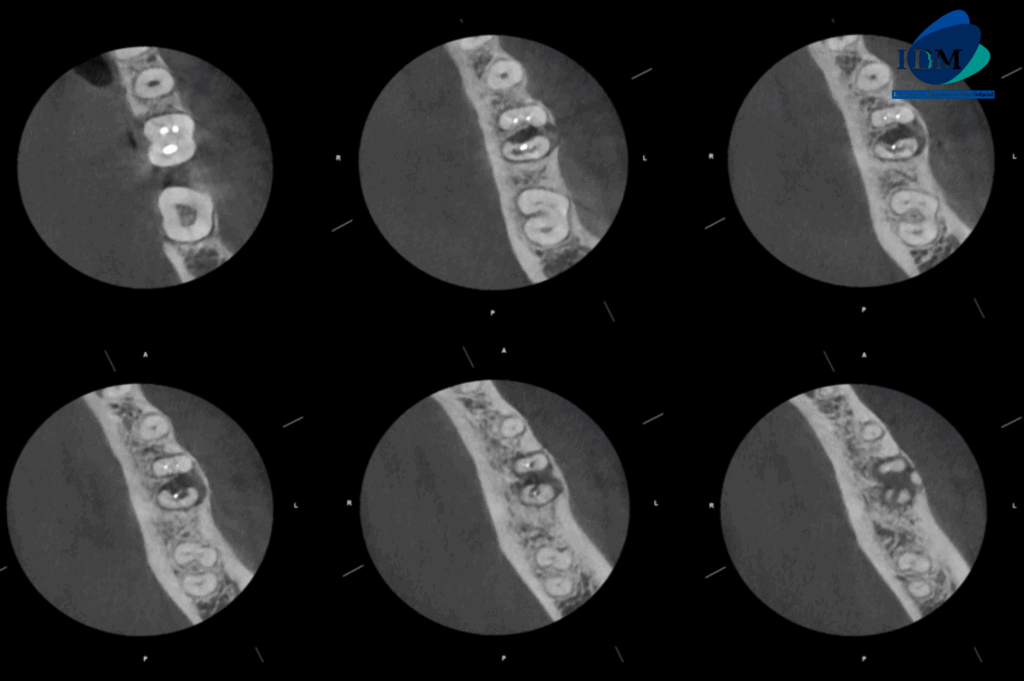

CORTES AXIALES

A la evaluación de la tomografía computarizada se puede observar el tratamiento de conductos de ambas raíces, sim embargo el conducto distal presenta una obturación orientada hacia la superficie interna a nivel de tercio medio radicular (vista en cortes axiales), asimismo observamos en cortes tangenciales la reabsorción radicular externa de la raíz distal que compromete el tercio medio y apical. La raíz mesial presenta reabsorción radicular externa de tercio apical. Finalmente se evidencia compromiso de la tabla ósea lingual (cortes transaxiales) y osteítis condensante circundante.